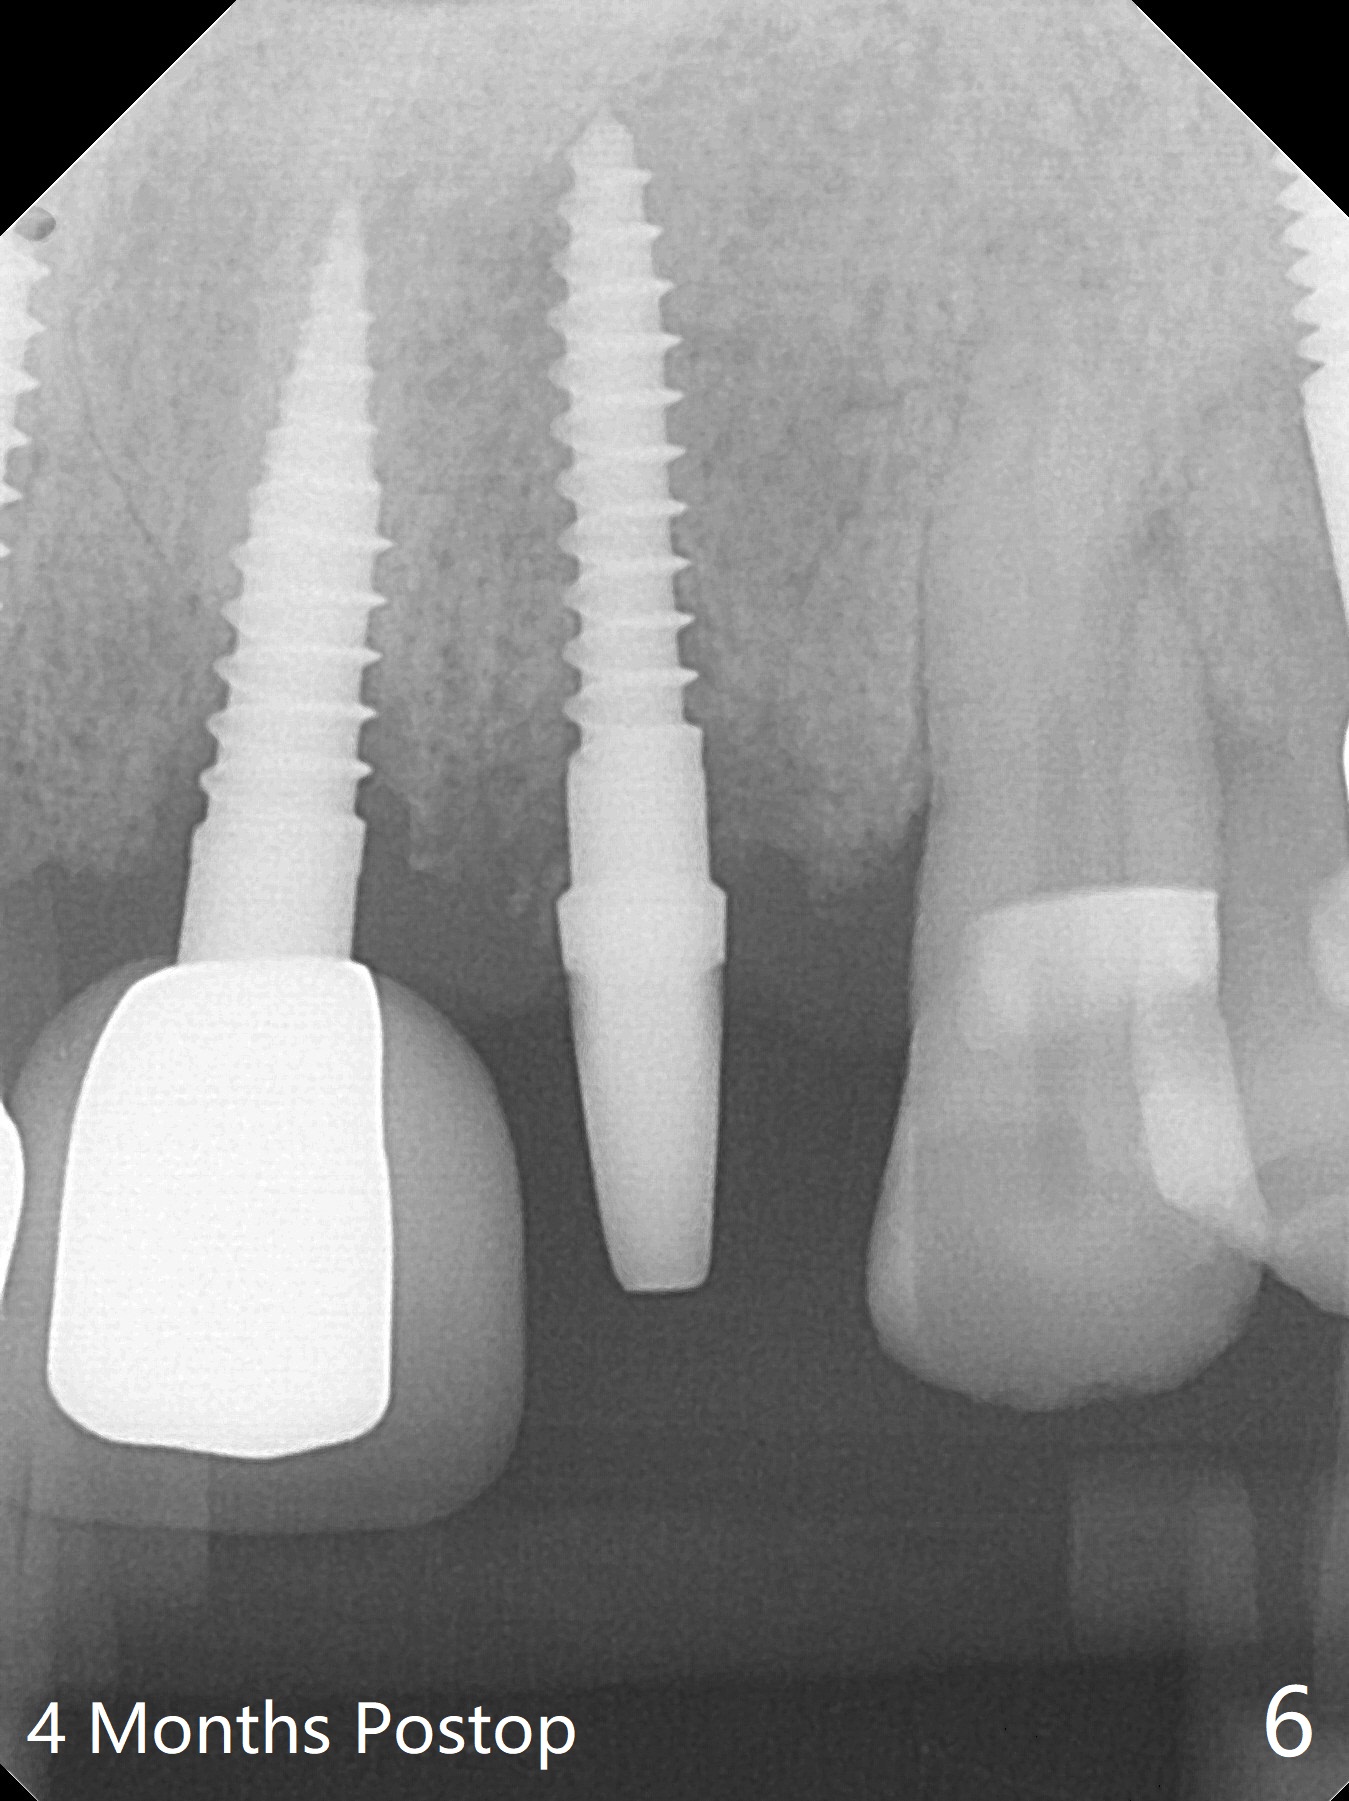

A 64-year-old man requests implant for the loose tooth at #10. The bone width is 5.5 mm (Fig.1); with 2.5 mm implant, there is 1.5 mm of the bone on the either side of the implant. The ideal width is 2 mm, which is safe, preventing buccal or palatal plate perforation. The buccal crest is lower when the tooth is extracted (Fig.4). Following trajectory confirmation (Fig.2), a 2.5x12(2) mm implant is placed a little deeper than expected to ensure no implant thread exposure with bone graft (Fig.3,5). The bone loss at #8 and 9 (Fig.2,3) is associated with the narrow ridge. The surface treatment of 1-piece implants is not as good as that of regular ones. The threads appears to be covered by the bone or bone graft 4 months postop (Fig.6).